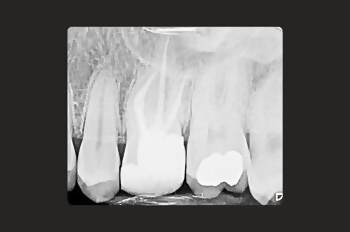

Root canal treatment allows your dentist to remove the infection before it can cause irrevocable damage. It’s a tooth-saving procedure that very often saves a tooth from needing to be extracted.

Your tooth is disinfected and sealed, preventing further bacteria from compromising its structure and health.

An infected root canal can cause intense pain, abscess formation, tooth loss, and even the infection spreading to other parts of the body if left untreated.